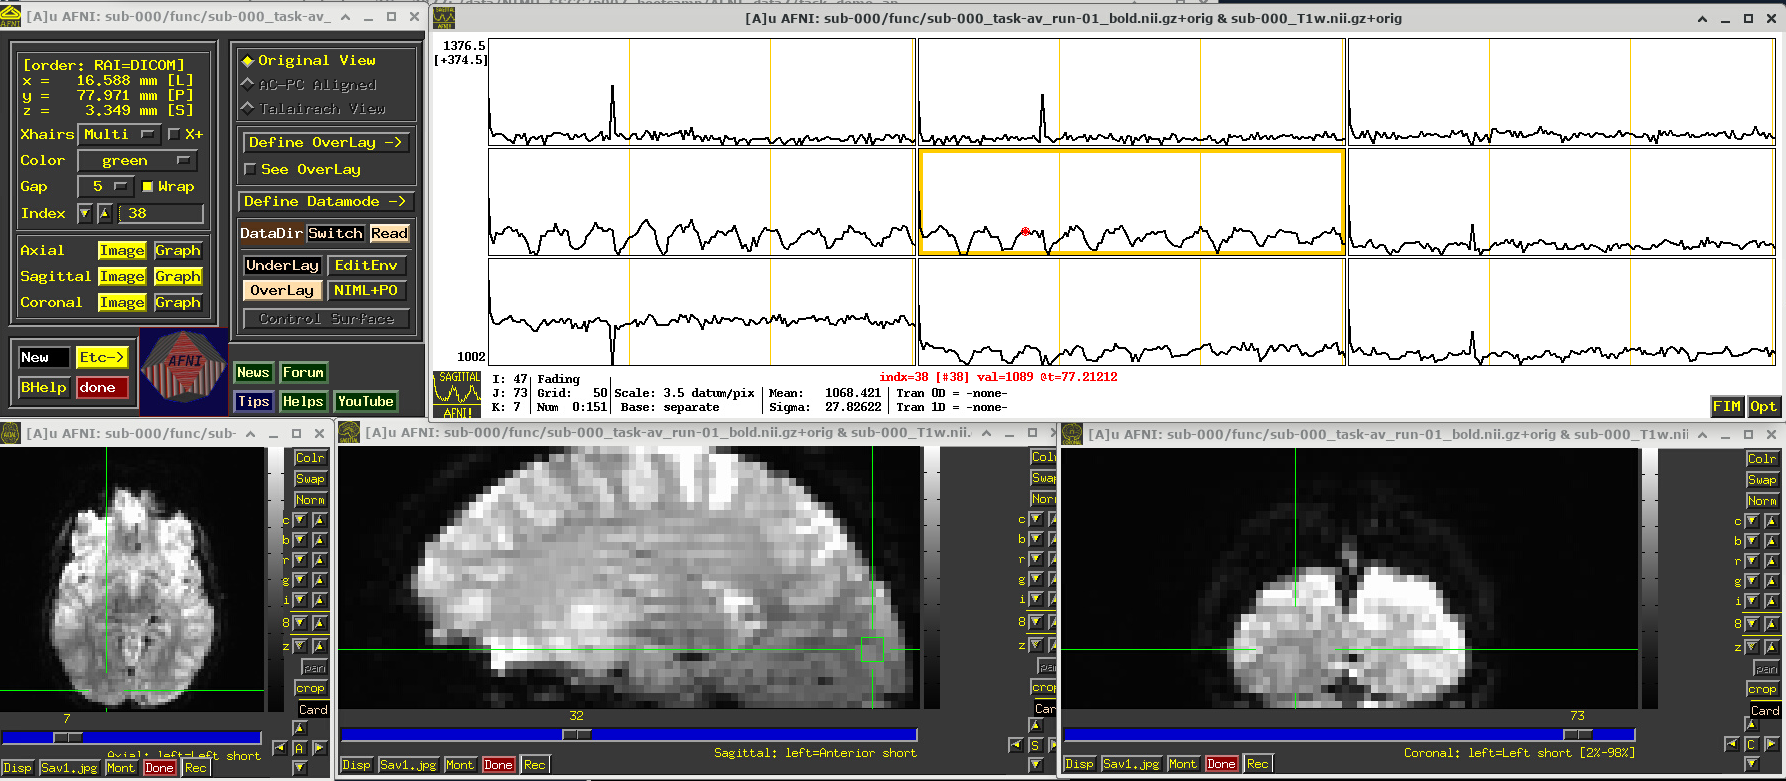

Click around and see how different parts of the brain appear. For example, if you end up at the location (x,y,z) ~ (8, 31, 60), you will see some spikes that are very big relative to the other fluctuations. These are due to a subject motion event about a quarter of the way through the run.

Some spikes are up, some are down, and some time series don’t appear to have any. This heterogeneity of motion-induced spikiness is one major reason why participant motion is so hard to navigate well in processing and analysis.

Up above, and here as well, you might also notice a subtle thing that appears in all time series at their very start—a different kind of spike. (It is hiding a bit, because of the y-axis there, but look closely.) This one is different because it is always upwards, uniformly. This has a different root cause. Each dataset looks normal there as a 3D volume, but in fact the recorded values are uniformly higher in the first few volumes than the rest—this is a “pre-steady state” phenomenon. It occurs generally in FMRI as the acquisition sequence settles into a steady state. Some scanners or initial data-streams clip out these time points, while others don’t. It is good to be aware that these can occur.

You can tell afni_proc.py to remove the first few EPI volumes, if the input data does include such pre-steady state volumes. And afni_proc.py will automatically check and warn you if it appears that the user did not account for some pre-steady state volumes that appear to be present. (And we note that participant motion can occur in the first few volumes, so sometimes it is hard to tell which affect might be happening, or if both are.) In any case, you need to make sure that your task-based timing files stay synchronous with the EPI datasets as processed!

# Display a screenshot of the AFNI GUI with the first EPI run loaded, checking out spikes

IPython.display.Image(filename='example_snapshots/img_02_afnigui_epi_r01_spikes.png')

../_images/46131ddfd698370db628152f22b5707ca1f78f9b0515788c32fe949500047e05.png